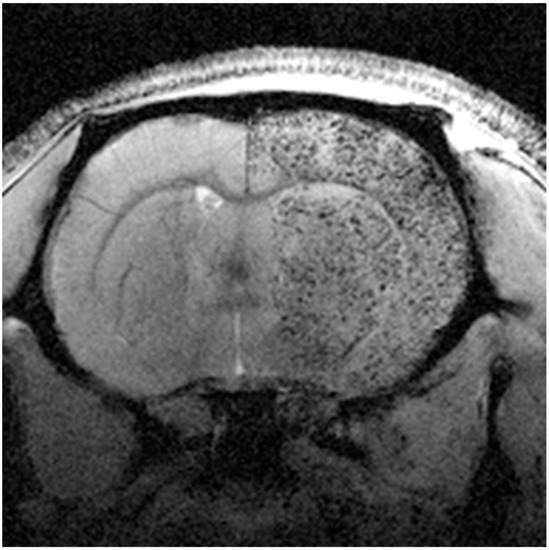

- Argibay, B.; Trekker, J.; Himmelreich, U.; Beiras, A.; Topete, A.; Taboada, P.; Pérez-Mato, M.; Vieites-Prado, A.; Iglesias-Rey, R.; Rivas, J.; et al. Intraarterial route increases the risk of cerebral lesions after mesenchymal cell administration in animal model of ischemia. Sci. Rep. 2017, 7, 40758. [Google Scholar] [CrossRef]

| MRI cell tracking | Superparamagnetic iron oxide nanoparticles (SPIONs) | Cell tracking of mesenchymal stem cells (MSCs) | [97] |